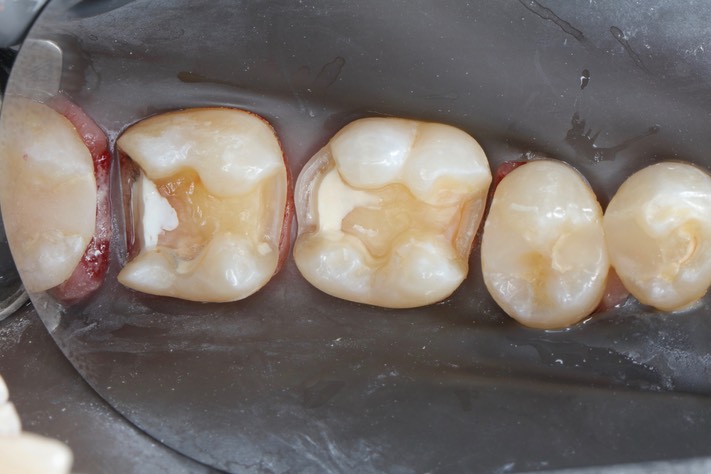

Dr. May Chang’s cases

March 1, 2012

February 2, 2012

January 5, 2012

Hilo November 4 and December 3, 2011

Gary Umeda #30-31 prep